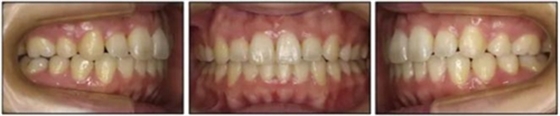

1.基本信息:女性,24歲2月,主訴上前牙及上唇不美觀(圖1)。因美觀問題不愿使用上頜固定矯治器。

2.檢查:凸面型、骨性II類,安氏II類1分類錯(cuò)合畸形。面型正中對稱,下面高略高,頦部后縮,唇肌略緊張。無顳下頜關(guān)節(jié)癥狀,下頜運(yùn)動正常,無偏斜。上下頜中線與面中線相一致,所有恒牙存在,口腔衛(wèi)生可,牙周情況可?;颊呓】?,無系統(tǒng)性疾病,無牙科創(chuàng)傷史及不良習(xí)慣,懷疑遺傳因素導(dǎo)致錯(cuò)合畸形。

3.測量分析:治療前記錄提示該患者左右磨牙與尖牙為安氏II類關(guān)系,上頜牙弓重度擁擠,下頜牙弓輕度擁擠,深Spee曲線。6.3mm深覆蓋,80%深覆合。牙齒無齲,無第三磨牙。

治療后數(shù)據(jù)提示治療目標(biāo)達(dá)成。面相結(jié)果提示微笑及側(cè)貌得到改善(圖6)。達(dá)到了安氏I類尖牙關(guān)系和安氏II類磨牙關(guān)系,形成尖牙保護(hù)合。牙齒中線無偏斜,達(dá)到理想的覆合覆蓋,Spee曲線得到整平。